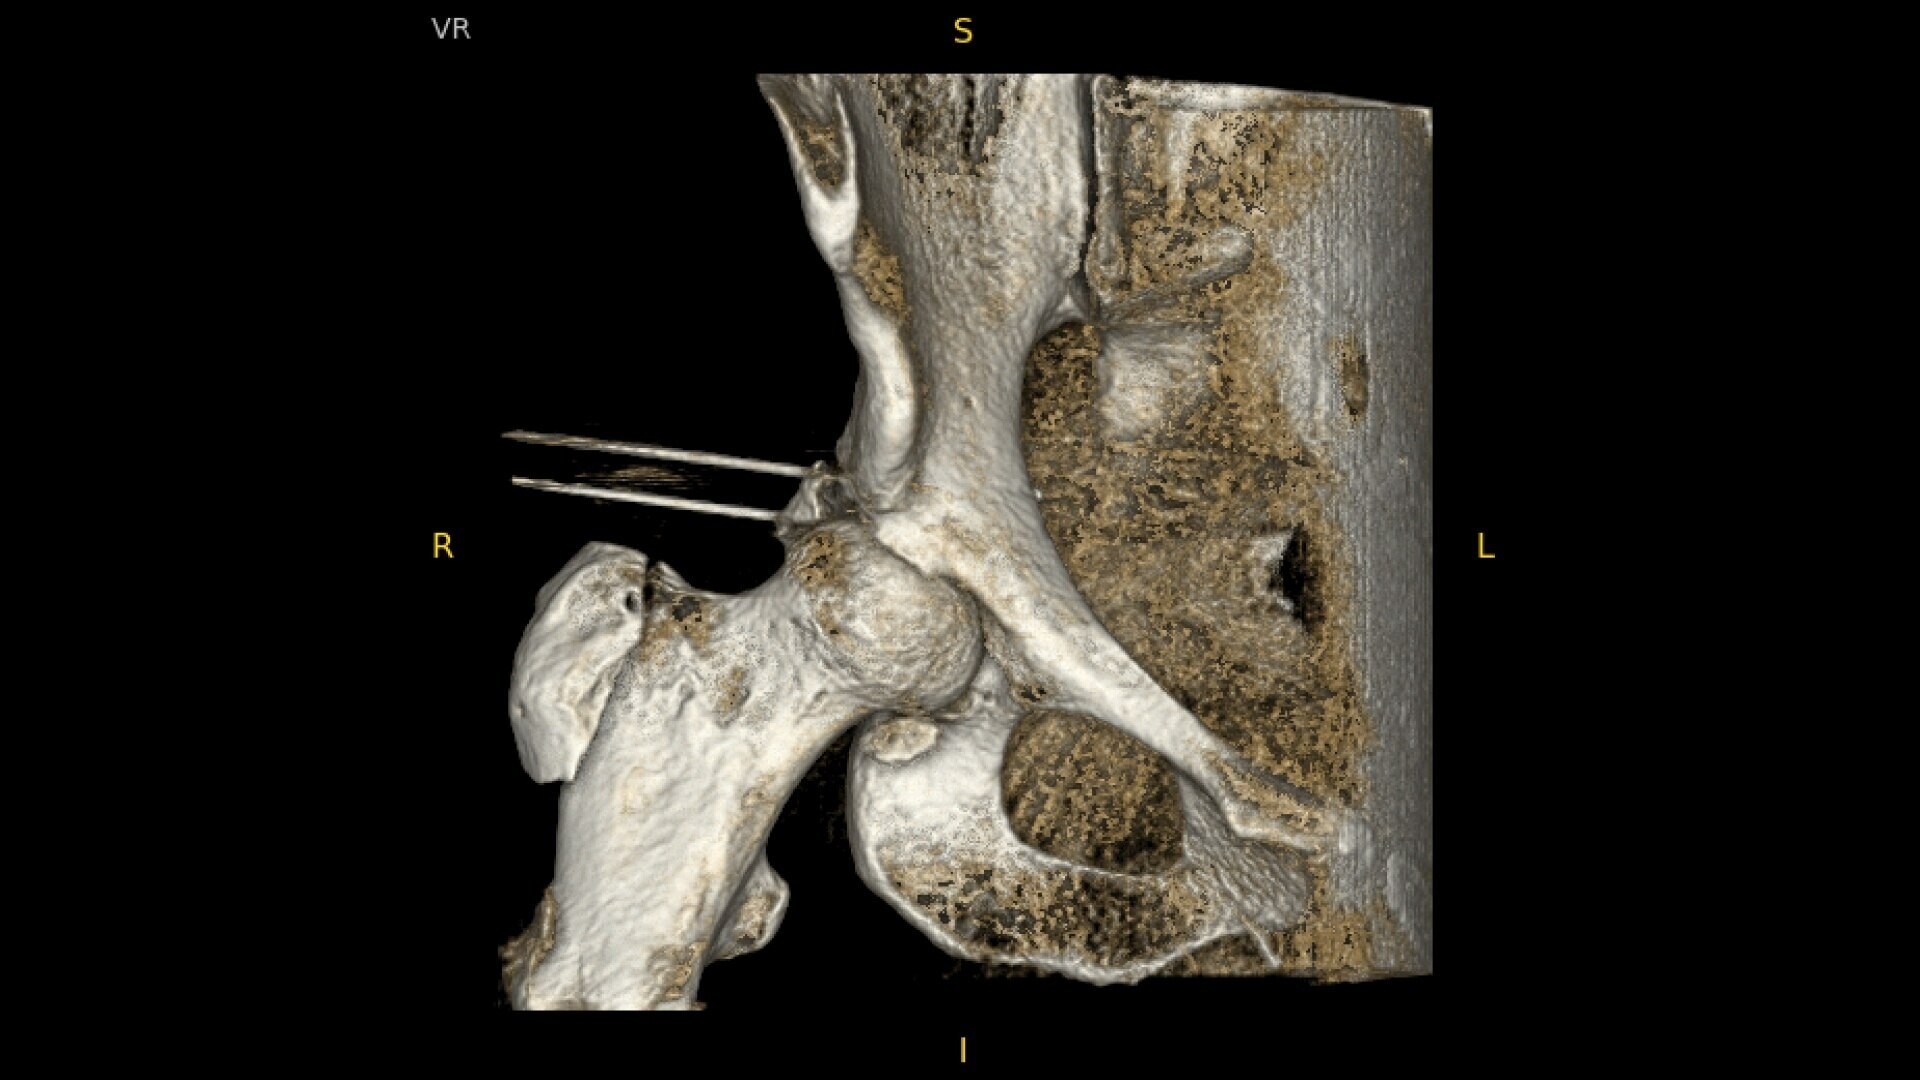

See precise anatomical detail of varying densities such as bone and soft tissue with a high dynamic range with the OEC Elite CFD with a flat detector, image processing advancements and 4K viewing display.

During hip or femur imaging, capture up to 22% more Field of View by positioning detector closer to patient anatomy with the OEC low-profile X-ray tube housing compared to mono-block C-arms.

Complex orthopedic procedures require powerful imaging systems. OEC premium C-arms perform in a variety of procedures such as:

• Hip fracture fixation

• Hip replacement

Designed to bring high-definition 3D and 2D images to surgical suites and integrating into existing surgical workflows.